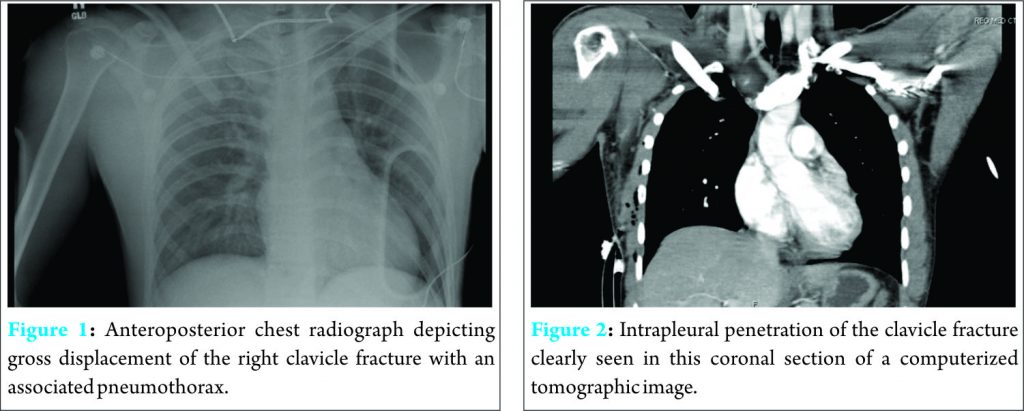

Radiographic analysis of his chest revealed a right proximal third clavicle fracture with inferior displacement complicated by a partial pneumothorax (Fig. 1). He had also sustained a displaced femoral shaft fracture. A chest thoracostomy tube was inserted emergently into the right pleural cavity and placed under suction to inflate the lung. Further radiographic studies including computerized tomography images confirmed that the fractured clavicle had penetrated the pleural cavity and caused a partial lung collapse (Fig. 2). The patient was initially placed in a sling for the clavicle fracture to allow access to the thoracostomy site.